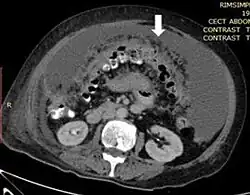

| Axial abdominal computed tomography featuring omental caking due to peritoneal carcinomatosis | |

Omental cake is a radiologic sign indicative of an abnormally thickened greater omentum.[1] It refers to infiltration of the normal omental structure by other types of soft-tissue or chronic inflammation resulting in a thickened, or cake-like appearance.[2]

Due to the variety of symptoms experienced by patients with omental caking,[5] omental cakes are most frequently discovered on abdominal computed tomography (CT) or ultrasound. Plain film radiography (X-ray) is not a suggested modality for investigating the spread of cancerous cells in the abdomen due to the poor spatial resolution amongst soft-tissue densities. Contrast resolution obtained through CT allows radiologists to investigate omental caking for morphology, intraperitoneal fluid, and regional lymphadenopathy assists in proper diagnosis so clinicians, surgeons, and oncologists can plan the appropriate course of treatment.[8]